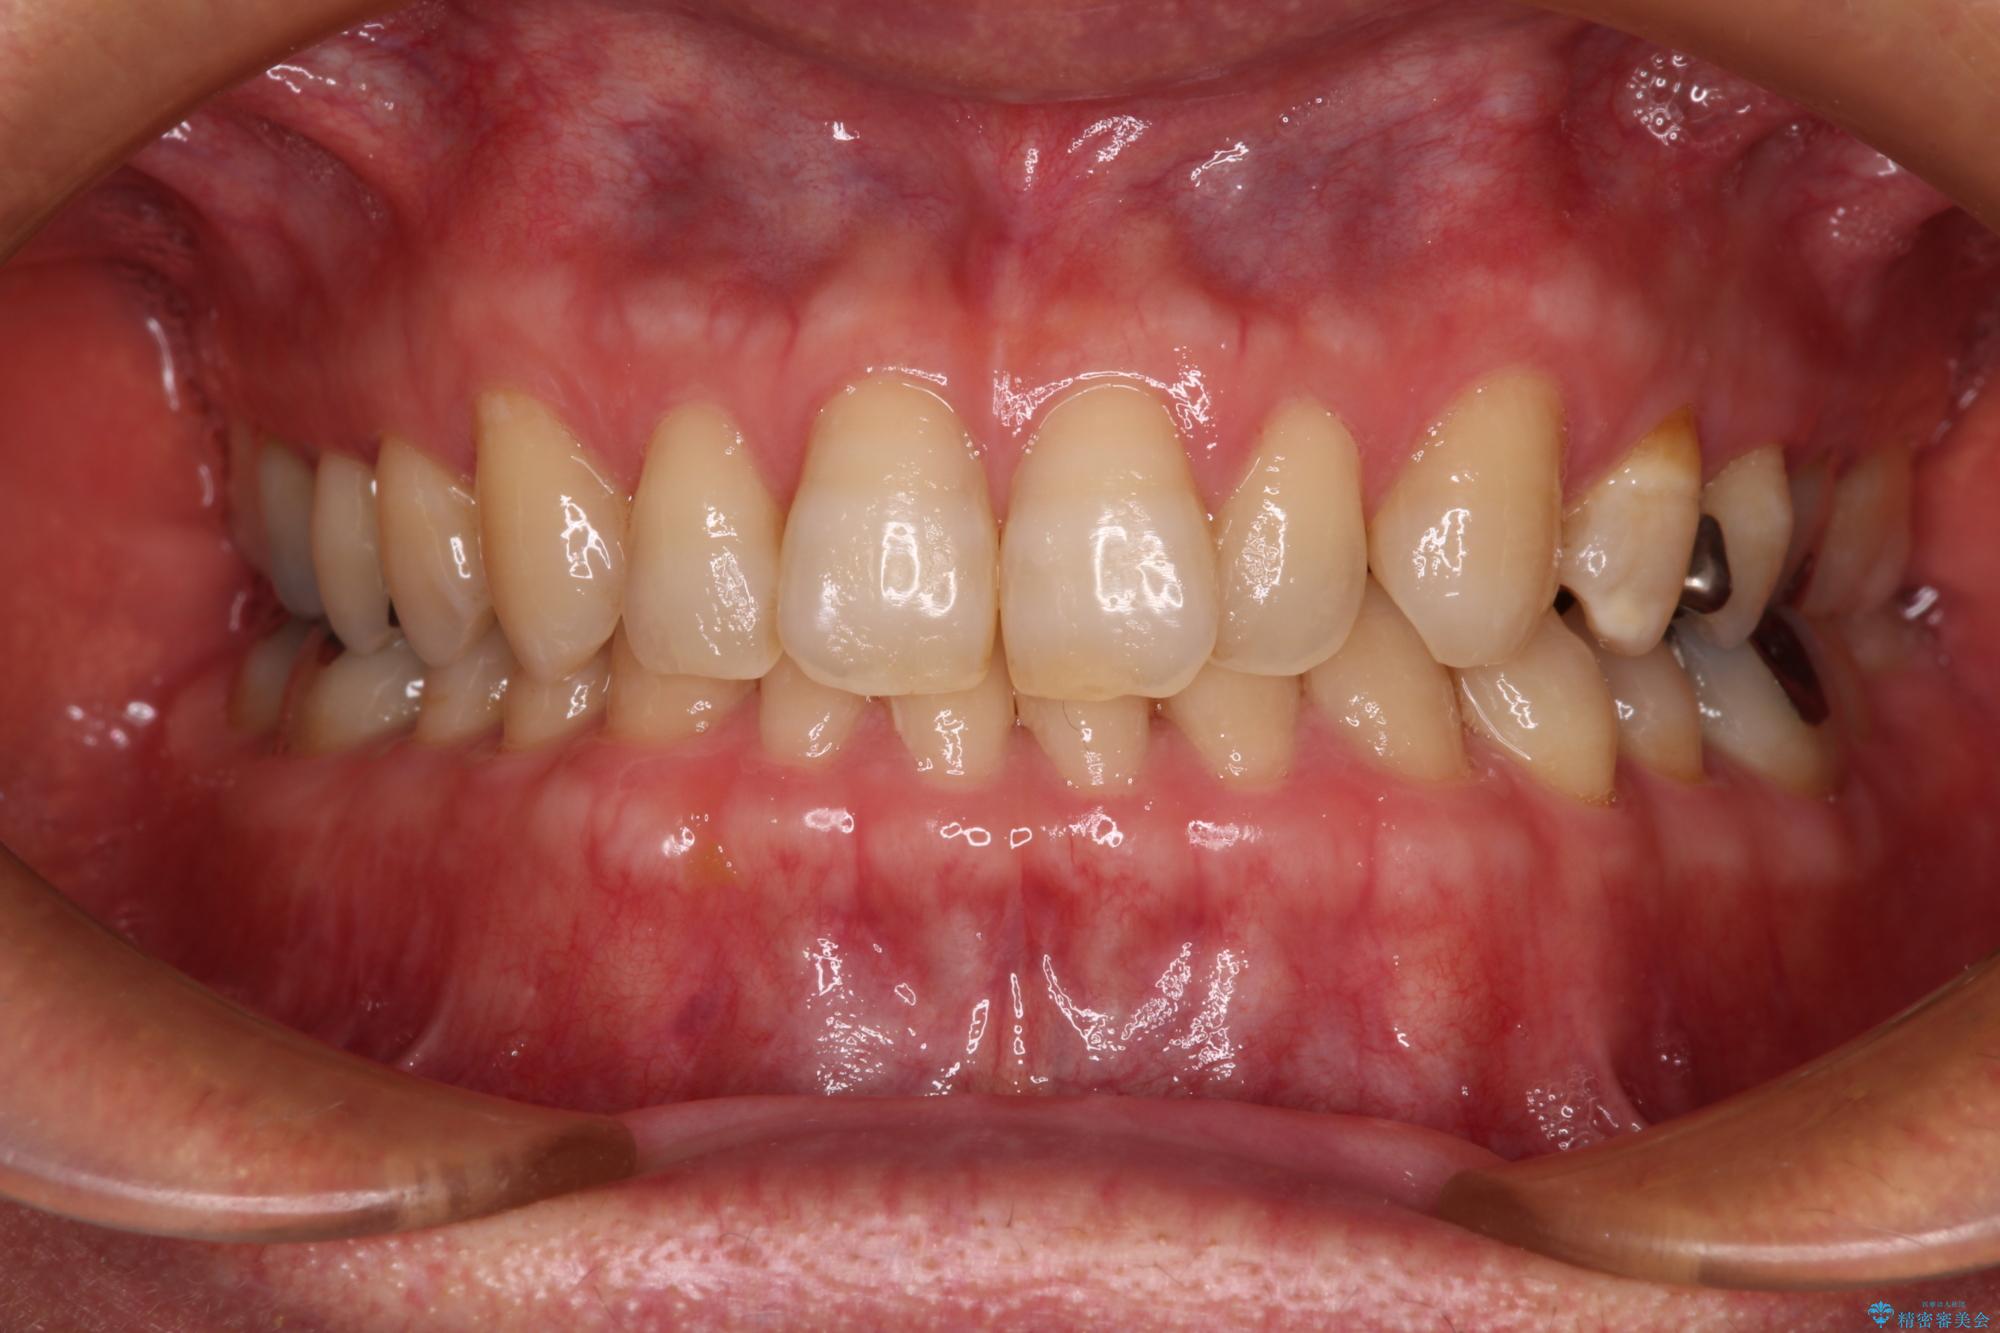

- 前歯のデコボコと隙間の空いた歯列を気にして来院された患者様です。

下顎前歯が隠れるほどのディープバイトにより、強い咬合力と突き上げで上顎歯列に隙間が空いている状態でした。